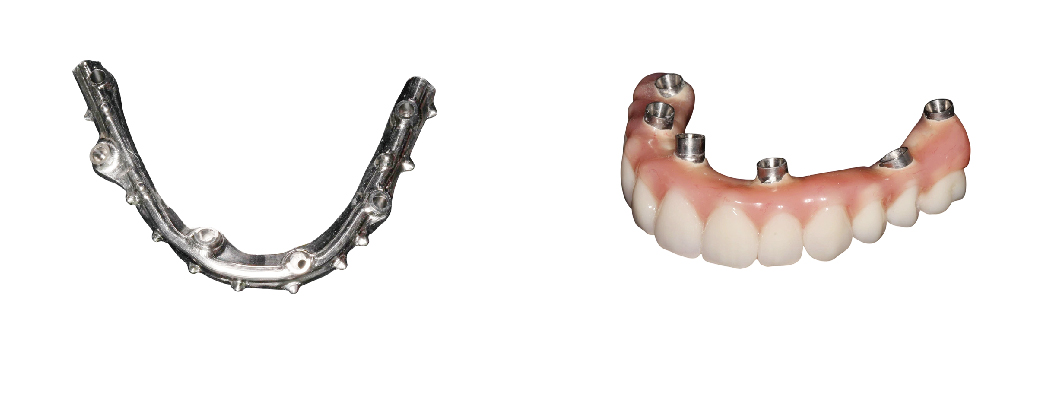

透過四支或六支植體的全口重建治療概念,採用直式和傾斜方式植入植體。後方傾斜植入的植體可以避開下顎的神經線與上顎的鼻竇位置,降低垂直骨量的需求。

不同於一般傳統植牙使用垂直式植體,All-on-4 / 6 一日全口重採用傾斜式植體,所需牙骨量較少,特別適合骨質流失嚴重的病人使用。

另外,牙肉萎縮嚴重的病人也適合接受 All-on-4 / 6一日全口重建,其使用的假牙可模擬牙肉部分,以完美的牙、肉比例加以擴充,安裝後美觀加分,效用超越傳統活動式假牙。